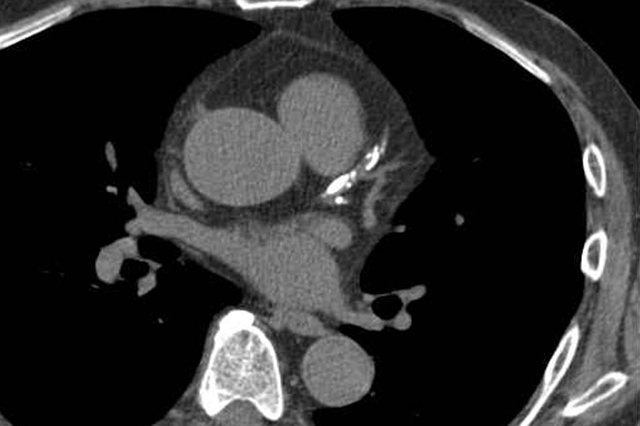

5. 복강 및 혈관계 질환

- 복부 대동맥류(AAA): 대동맥의 일부가 풍선처럼 부풀어 오르는 질환으로, CT는 직경 확대와 벽 석회화, 혈전 형성을 명확히 보여줍니다. 파열 위험성 평가에도 활용됩니다.

- 복강 내 출혈: 외상, 파열, 종양, 항응고제 복용 등으로 인한 내출혈은 CT에서 조영제 누출 형태로 나타나며 응급 진단이 가능합니다.